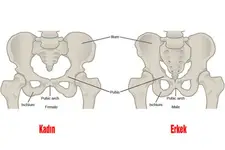

- Düzenli egzersiz yapmak, kemik sağlığını güçlendirmek için önemlidir. Özellikle ağırlık taşıyan aktiviteler, kemik yoğunluğunu artırabilir.- Sigara içmek ve aşırı alkol tüketimi, kemik sağlığını olumsuz etkileyen faktörlerdir. Bu alışkanlıklardan kaçınılması önerilmektedir.- Kadınlar, menopoz sonrası dönemde osteoporoz riski yüksek olduğundan, düzenli kemik taramaları yaptırmaları önerilir.- Genetik yatkınlık, bazı kemik hastalıklarının oluşumunda etkili olabilir. Aile geçmişi dikkate alınarak, bireyler kendilerini bu konuda bilgilendirmelidir.